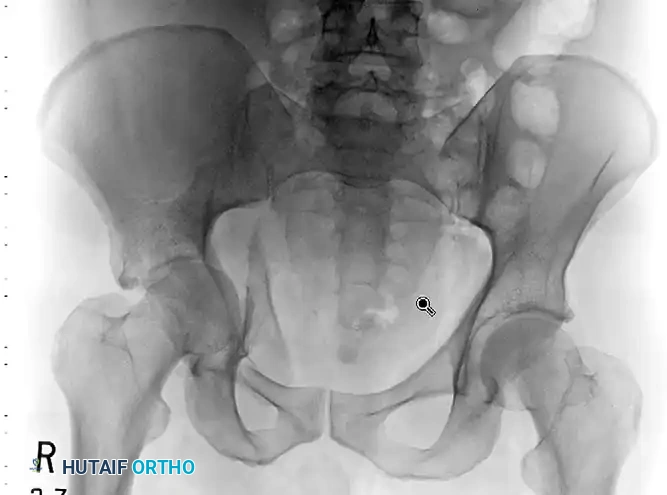

FIGURE 56-33: Anterior column fracture with quadrilateral surface comminution treated through an ilioinguinal approach with the Stoppa interval utilized to stabilize the quadrilateral surface.